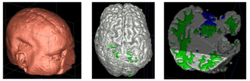

We are working on an extension of the "atlas-based classification" method ABC [1] for TBI datasets with the clinical goal to efficiently segment healthy brain tissue and cerebral lesions. A main goal will be the automated segmentation of healthy brain tissue and user-assisted segmentation of various cerebral lesion types (hematoma, subarachnoid hemorrhage, contusion and DAI, perifocal (regional) to diffuse (generalized) edema, hemorrhagic diffuse axonal injury (DAI)and more. A strong emphasis will be on the joint of multiple imaging modalities (T1 pre- and T1 postcontrast, T2 (TSE), FLAIR, GRE, SWI, Perfusion, and DTI/DWI) for improved detection and quantitative characterization of lesion types.

Multimodal MRI data of TBI patient.

We conducted experiments with the application of the ABC tool to multi-modal image data of 5 TBI cases provided by DBP partner UCLA. The tool includes co-registration of multiple modalities via mutual-information linear registration, and a nonlinear registration (high-deformable fluid registration) of a probabilistic normative atlas for segmentation of healthy tissue. The following results show feasibility of multi-modal registration and segmentation of normal tissue. Pathology is currently segmented via postprocessing using 3D user-supervised level-set evolution.